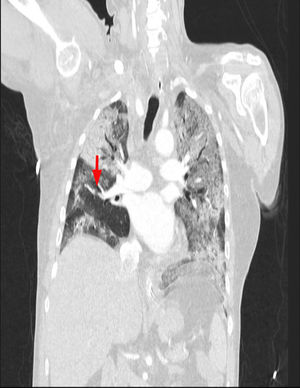

Paciente de 64 años, como único antecedente personal hipertenso, ingresa en la UCI con diagnóstico de SDRA grave secundario a neumonía bilateral por COVID-19. En radiografía de tórax se observa un patrón alveolointersticial bilateral que afecta más al pulmón derecho, sobre todo al campo medio (fig. 1, indicadores flechas). En la analítica destaca un dímero D muy elevado (28.970ng/ml) y ante la sospecha de TEP se realiza ecocardiografía transtorácica apreciándose sobrecarga de presión de VD con signo de McConnell positivo. Dado los hallazgos ecocardiógrafos, se inició tratamiento anticoagulante con heparina de bajo peso molecular (enoxaparina 1mg/kg/cada 12h) y se solicitó angio-TAC torácica para confirmación diagnóstica, evidenciándose defecto de repleción en arteria del segmento lateral del lóbulo medio (flechas en figuras 2 y 3) en relación con TEP. Además existe una afectación difusa bilateral y extensas áreas de patrón en empedrado en relación con el proceso infeccioso vírico (figs. 2 y 3). Se mantuvo el tratamiento anticoagulante hasta el alta sin complicaciones hemorrágicas asociadas.